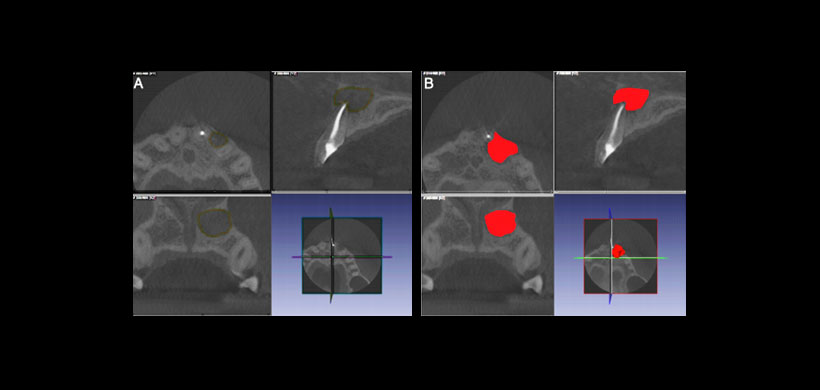

El propósito de este estudio fue desarrollar y evaluar la validez predictiva de un análisis volumétrico de los quistes periapicales basado en CBCT solo o combinado con criterios radiológicos designados. ( Figura 1)

Figura 1: Tomografía volumétrica de quiste periapical.

El análisis por tomografía computarizada por haz de cono (CBCT) permite la evaluación tridimensional de lesiones perirradiculares y puede facilitar el tratamiento de quistes periapicales.

Para lo cual tres examinadores independientes evaluaron 118 escáneres CBCT prequirúrgicos de casos que se sometieron a apicectomías y tenían un diagnóstico estándar histopatológico de un quiste o granuloma. El volumen de la lesión, la densidad y las características radiológicas específicas se evaluaron utilizando software especializado.